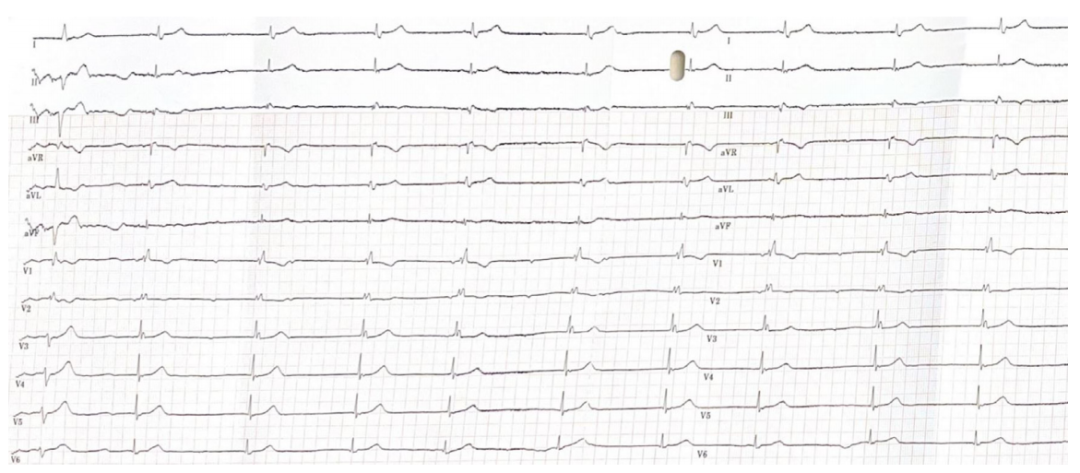

(TTE)检查。12导联心电图

显示间歇性完全性心脏传导阻滞伴交界性逸搏心律,以及新发右束支传导阻滞(图1)。

图1 入院心电图